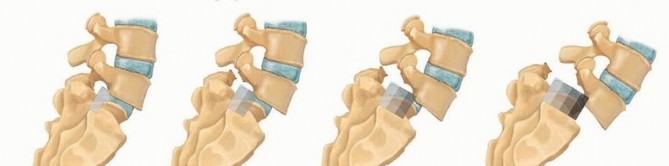

FIG 1 • A. The dysplastic and isthmic types of spondylolisthesis. B. The Meyerding classification is based on degrees of slippage: grade I, 0 to 25%; grade II, 26% to 50%; grade III, 51% to 75%; grade IV, 76% to 100%.

Pars interarticularis is “the place between two joints”.17 Most spondylolisthesis cases are of dysplastic (congenital), isthmic, and degenerative types. Degenerative listhesis is common in adults and most commonly seen at L4-L5 level. The dysplastic and isthmic types most commonly affect L5-S1 level and are usually seen in children (

FIG 1A

).

The Meyerding classification is used to quantify the severity of slippage (

FIG 1B

*) and has five grades19: Grade I: 0% to 25% slip

Grade II: 26% to 50% slip

Grade III: 51% to 75% slip

Grade IV: 76% to 100%

Grade V: corresponds to spondyloptosis